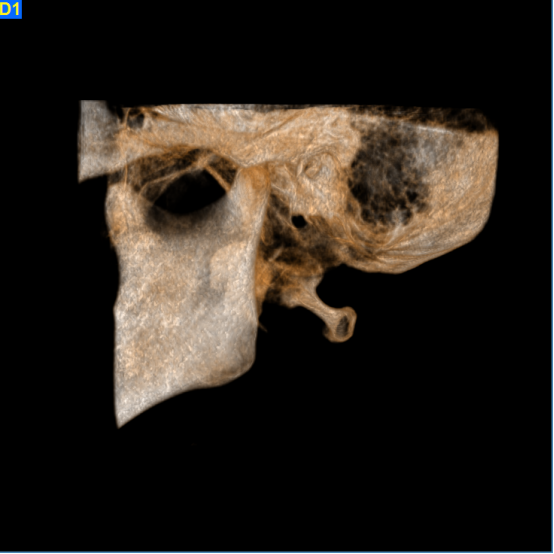

颞下颌关节检查单次扫描即可通过矢状和冠状图像观测到关节间隙的改变和是否发生病理变化。3D影像重建可以清晰提供颞下颌关节、关节头及关节颈部详细解剖信息。